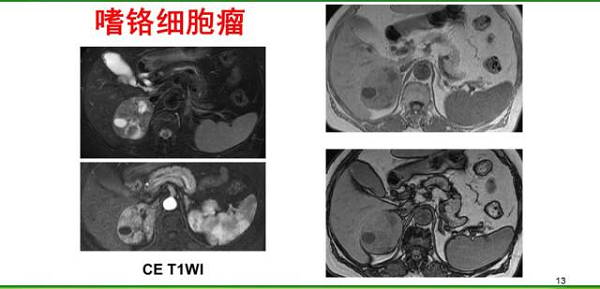

患者右側腎上腺區(qū)有一腫塊,右上為T1加權同相位圖像,顯示腫塊信號略低于肝組織,其內尚見更低信號區(qū)域;右下為T1加權反相位圖像,病灶信號無明確衰減。左上為T2加權圖,示該腫塊呈現(xiàn)中等高信號,其內見明顯高信號囊變區(qū)。

該病例MRI平掃已經明確檢出了腫塊,但定性診斷仍很困難。增強掃描以后,可見該腫塊明顯高強化,第一考慮是嗜鉻細胞瘤。該患者并無高血壓癥狀。臨床上約有15%到20%的嗜鉻細胞瘤患者無明確的高血壓癥狀,這些患者手術風險會更大。增強掃描提示了嗜鉻細胞瘤的診斷,術前做了精心準備,患者安全地完成了腫瘤切除,病理證實為嗜鉻細胞瘤。